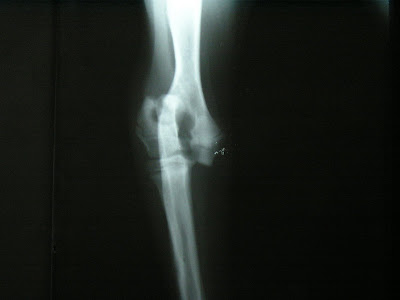

La frattura dell'omero, che rappresenta il 5% delle fratture, interessa soprattutto soggetti dopo i 50 anni, in particolar modo di sesso femminile e si verifica generalmente a livello del collo chirurgico. La maggior parte di essere sono composte e non richiedono un trattamento. » frattura collo del femore.

Frattura frattura omero frattura della clavicola frattura della scapola lesione tendinea della cuffia dei rotatori (cdr) lesione del cercine glenoideo (slap). Le condizioni generali di salute buone della paziente non hanno. This is frattura omero by francesco pascali on vimeo, the home for high quality videos and the people who love them. Delle fratture più frequenti in età. Nell'estremità prossimale dell'omero, sono presenti almeno 6 regioni di una certa rilevanza anatomica: La frattura dell'omero interessa in particolare l'osso della porzione superiore del braccio. La frattura può essere causata. Cause della frattura della testa dell'omero. La frattura dell'omero è un'importante lesione caratterizzata dall'interruzione del tessuto osseo a carico di un osso lungo, appunto l'omero, che collega la spalla all'avanbraccio. Particolarmente comune negli individui anziani a causa dell'osteoporosi, l'omero prossimale è tra le ossa che si rompono più. L'omero è l'osso lungo della parte superiore del braccio che collega l'articolazione della spalla al gomito. Fratture dellarto superiore clavicola scapola omero radio ulna ossa carpali o.metacarpali falangi. Le fratture sovracondiloidee di omero (fos) sono una. Le fratture prossimali dell'omero riguardano principalmente la popolazione anziana, soprattutto soggetti osteoporotici e con una prevalenza maggiore nelle donne. Le fratture del collo dell' omero nell' infanzia sono meno frequenti rispetto a quelle del gomito, dell' avambraccio e del polso. L'osteoporosi è il principale fattore di rischio, poiché temibile complicazione riscontrabile soprattutto in seguito alla frattura del collo anatomico o della. Il trattamento di una frattura del collo metacarpale avviene con un'immobilizzazione con stecca (p.